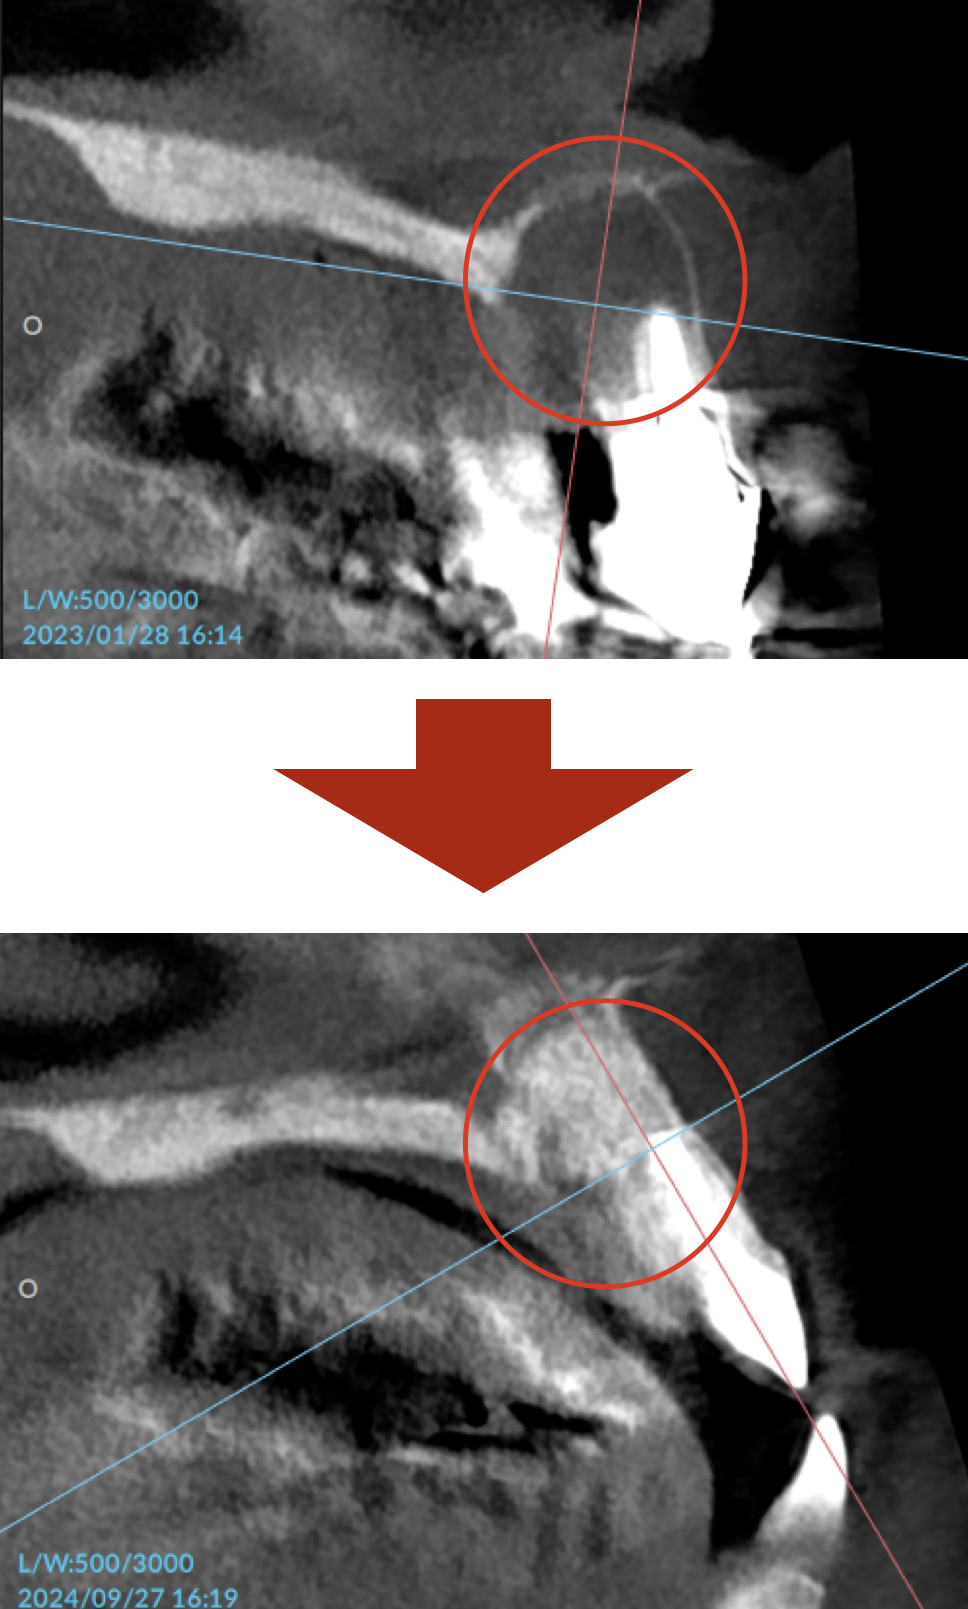

レントゲン・CTで撮影すると、上顎の前歯はかなり厳しい状態でした。

誰が見ても骨の喪失が明らかなほどで、抜歯は免れないレベルでした。

根管治療、そして骨補填剤を駆使して1年ほど。

喪失していた骨も再生し、見違える状態にまで回復しました。

これは治療をした私自身、とても驚いています。